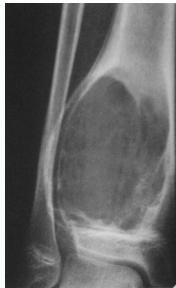

Aneurysmal Bone Cyst

- Child - young adult

- Metaphysis of long bone

- X-ray:

- Well-defined cyst

- Trabeculated

- Eccentrically placed

- Ballooning

- Bloody content

- Treatment:

- Curettage and bone graft

- Metaphysis, Eccentric